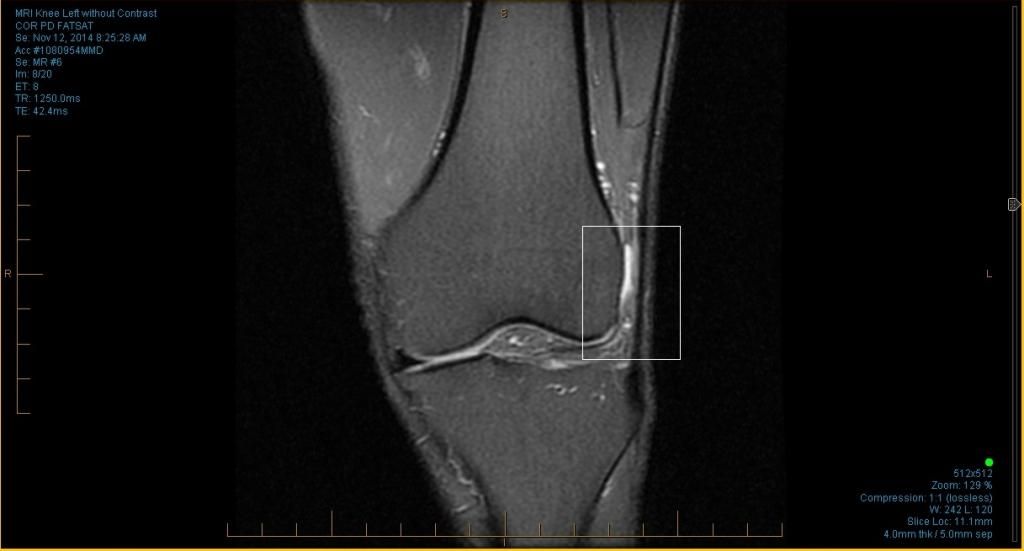

All I know is light colors could signify fluid…the light color is also whee i experience pain.

i tried looking for the corner in my images…and this is the best thing i could come up with (first image below with the red box).

I can read an MRI. It looks like your IT band is unhappy. You already knew that. Unfortunately the MRI can’t tell you how to fix it.